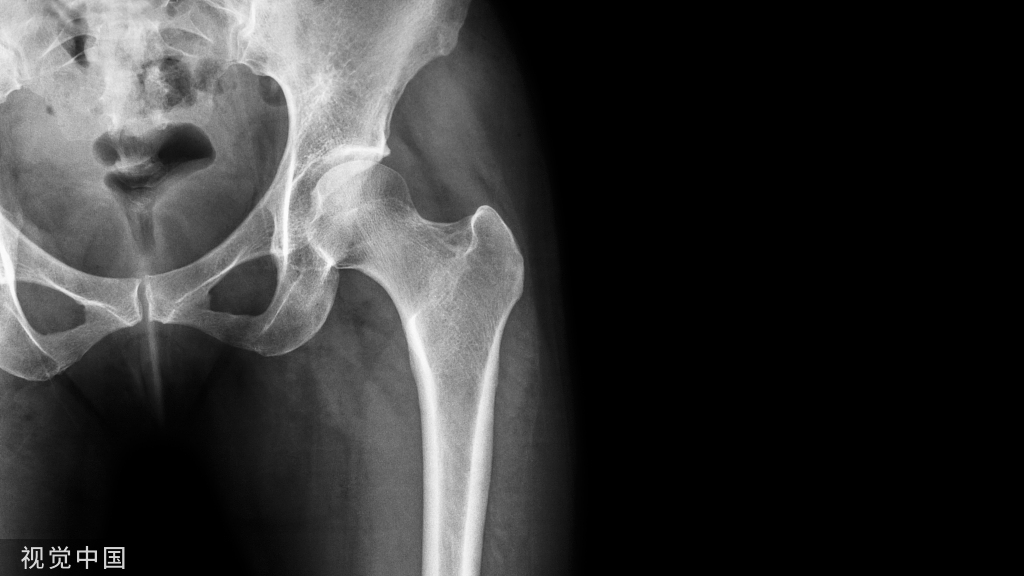

锁定钢板具有角稳定特性,这点与外固定架有点相似,因此,有学者创新性地将锁定钢板用于外固定,用于开放性骨折或感染性骨不连、骨缺损等的临时固定或终极固定。

锁定钢板具有角稳定特性,这点与外固定架有点相似,因此,有学者创新性地将锁定钢板用于外固定,用于开放性骨折或感染性骨不连、骨缺损等的临时固定或终极固定。现图文摘要综述如下: